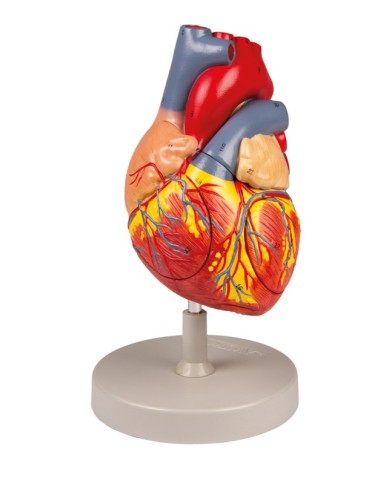

Qui trovi tutti i modelli anatomici di cuore dei più importanti produttori al mondo, 3B Scientific, Erler Zimmer e Somso.

Su Tuttoanatomia trovi la più ampia selezione di prodotti esistente sul web, che va dai cuori normali ai cuori affetti da patologie, per aiutarti a comprendere come le patologie cardiache influiscono e modificano la struttura anatomica cardiaca.

Per una migliore comprensione delle strutture anatomiche del cuore sono stati realizzati anche dei modelli anatomici di cuore ingrandito, si va dai piccoli ingrandimenti fino ai modelli di cuore per la formazione in aula, come il modello anatomico di cuore gigante prodotto da 3B Scientific: un modello di cuore ingrandito di ben otto volte.

Su Tuttoanatomia trovi la più vasta selezione online, certamente abbiamo il modello di cuore più adatto alle tue esigenze. I cardiologi e gli studenti acquistano i modelli anatomici di cuore umano per studiare nei minimi dettagli la struttura anatomica del cuore umano, ma anche per dare spiegazioni ai propri pazienti, per illustrare visivamente la patologia di cui sono affetti, ed il tipo di intervento che si intende eseguire durante la terapia. Le quotazioni su Tuttoanatomia sono le più convenienti del mercato e la qualità dei prodotti è davvero eccezionale, in modo da offrirti un rapporto qualità prezzo incomparabile.